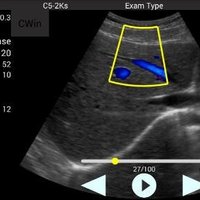

Konvexsonde (C5-2Ks) 3,3 MHz 2 - 5 MHz R50 Abdomen, Gynäkologie, Geburtshilfe, Urologie

• Color: B, M, 2B, 4B, THI, Color, Power, PW